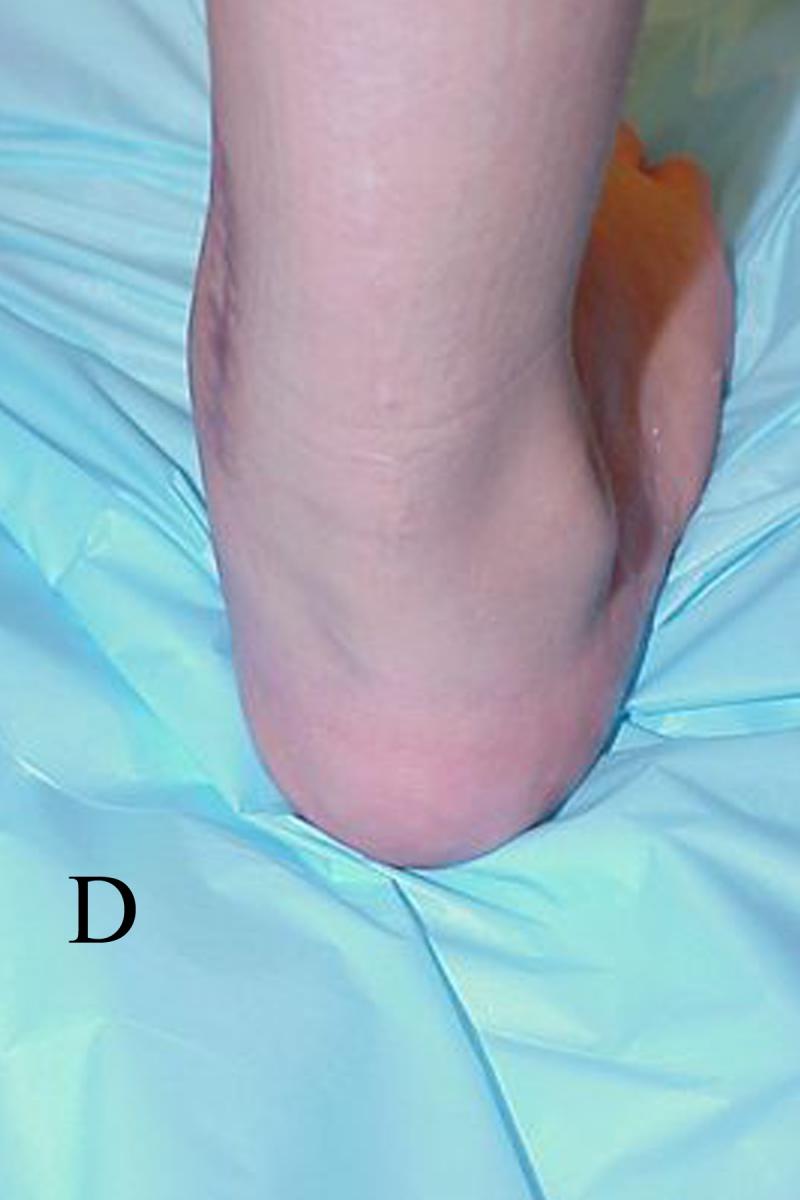

Ponseti also recognized an atypical form of talipes equinovarus. The major features of atypical talipes equinovarus are plantarflexion of both medial and lateral columns, short foot, rigid equinus, a deep plantar and medial midfoot crease, and a deep crease above the posterior heel. He considered these to be resistant, some syndromic, others teratologic, some neurogenic and occasionally iatrogenic. He modified the manipulation and casting protocol for these feet.

Fourth, until one has correctly aligned the forefoot and rearfoot, it is inappropriate to treat ankle equinus. Doing so has several undesirable consequences. Casting an unyielding equinus deformity will eventually damage the talar trochlear surface, making it flat and causing it to lose its sphericity. Ankle dorsiflexion will be mechanically limited. Rocker bottom deformity results from attempting to dorsiflex the rearfoot prematurely against the unyielding tendo-Achilles. Inflexible equinus causes the midfoot to dorsiflex against the rearfoot along the lateral column while the calcaneus remains in a plantarflexed position. This breaches the foot through the calcaneocuboid joint as well as the fourth and fifth metatarsal cuboid articulations.